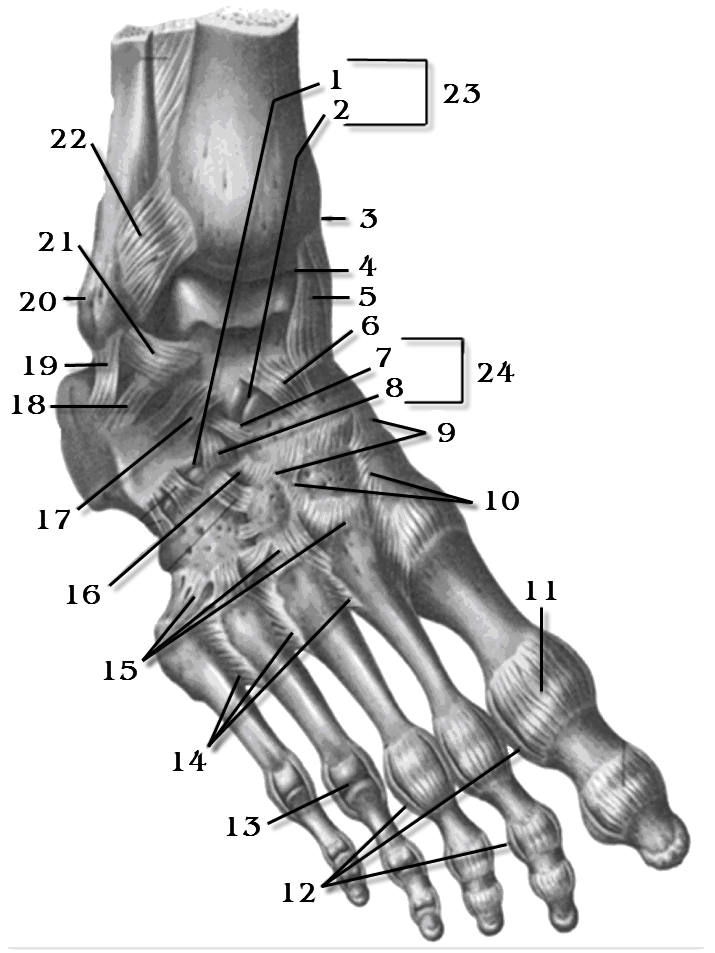

Анатомия голеностопа: Сухожилия и их строение